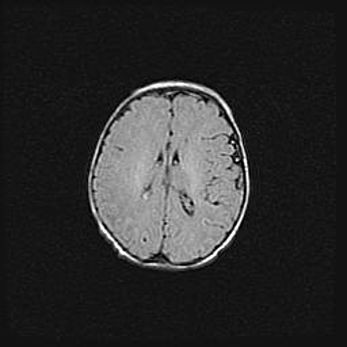

Открытая гидроцефалия.

Возраст: 9 месяцев 12 дней

Вес: 6800 г

Пол: мужской

Окружность головы: 41,5 см

Срок гестации: 28 недель

Гидроцефалия головного мозга у новорожденных имеет характерный признак: опережающий рост окружности головы приводит к визуально хорошо определяемой гидроцефальной форме сильно увеличенного в объёме черепа. Детские неврологи определяют следующие симптомы гидроцефалии у грудничков: выбухающий напряжённый родничок, частое запрокидывание головы, смещение глазных яблок к низу.